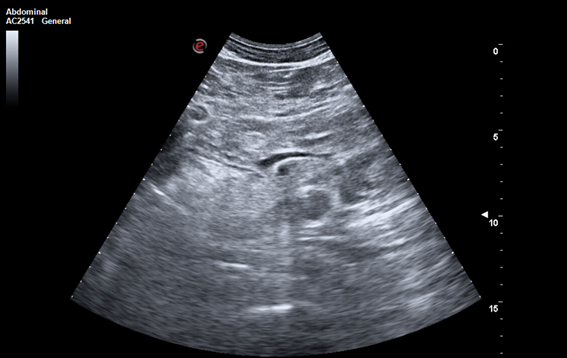

Descripción de los hallazgos ecográficos y las imágenes más relevantes para la resolución del caso.